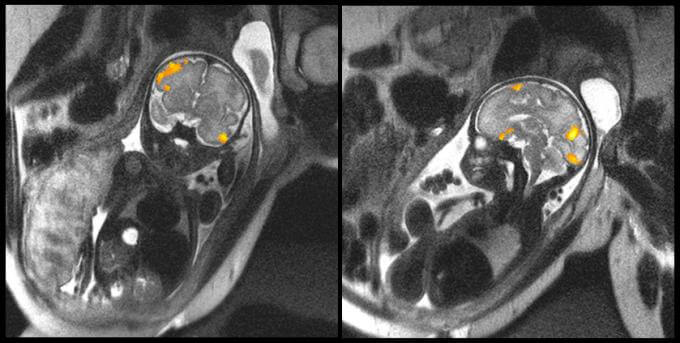

In the image above, we can see the MRI of a fetus at 20 weeks and other of one at 40 weeks. They are images obtained by the faculty of the Wayne State University School of Medicine in Michigan that clearly illustrate the fetal brain activity of these two babies while in their mothers’ wombs.

One of the scientists’ main objectives with this type of test is to study how the neurons of babies are connected during the last weeks of gestation. The data obtained reveal aspects that, until now, were unknown about premature babies.